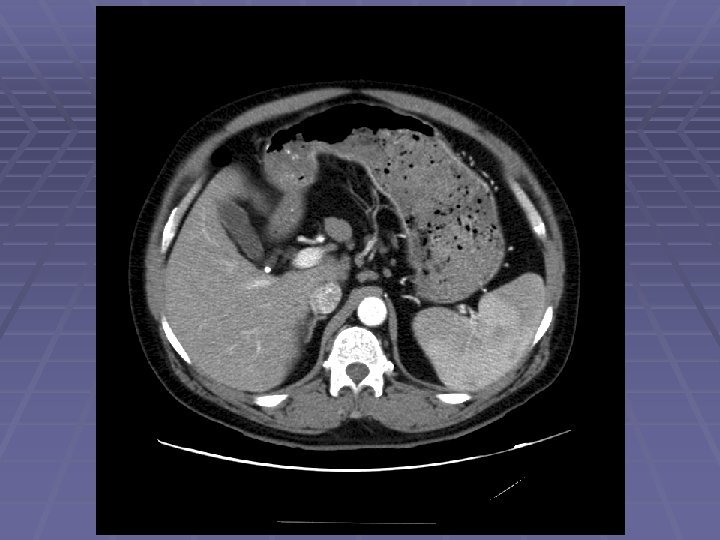

Liver Mass

FNA of Liver Mass

EUS Evaluation of Left Lobe of Liver

EUS in Malignant Disease Non-small cell lung cancer Pancreatic cancer Esophageal and gastric cancer Cholangiocarcinoma Rectal adenocarcinoma Metastatic disease Lymph nodes: aortopulmonary, subcarinal, paraesophageal, celiac, intra-abdominal Left lobe of liver Left adrenal And beyond – right lobe of liver, right adrenal, . . .